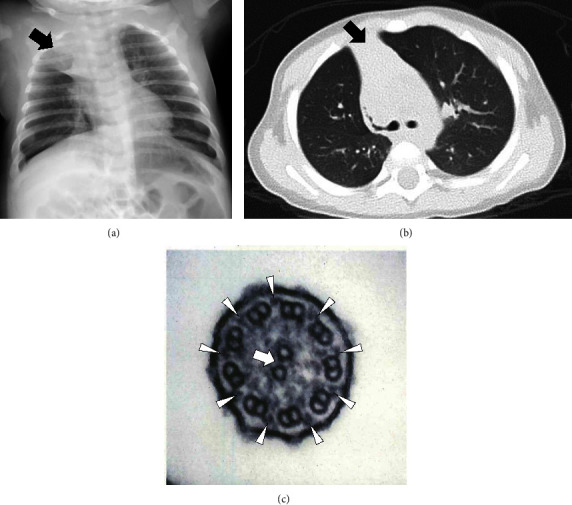

原发性纤毛运动障碍(PCD)是一种由纤毛运动相关基因引起的遗传性疾病。我们报告了两例由 OFD1 中心粒和中心极卫星蛋白(OFD1)基因半杂合子致病变体引起的 PCD 男性儿科病例。变异基因为 NM_003611.3:病例 1 中的 c.[2789_2793delTAAAA] (p.[Ile930LysfsTer8]) 和病例 2 中的 c.[2632_2635delGAAG] (p.[Glu878LysfsTer9]) 。两个病例都有反复呼吸道感染的特征。我们发现了一个变异体(c.2632_2635delGAAG),以前从未在任何 OFD1-PCD 病例中报道过。

Primary ciliary dyskinesia (PCD) is a hereditary disease caused by genes related to motile cilia. We report two male pediatric cases of PCD caused by hemizygous pathogenic variants in the OFD1 centriole and centriolar satellite protein (OFD1) gene. The variants were NM_003611.3: c.[2789_2793delTAAAA] (p.[Ile930LysfsTer8]) in Case 1 and c.[2632_2635delGAAG] (p.[Glu878LysfsTer9]) in Case 2. Both cases had characteristic recurrent respiratory infections. Neither case had symptoms of oral-facial-digital syndrome type I. We identified a variant (c.2632_2635delGAAG) that has not been previously reported in any case of OFD1-PCD.